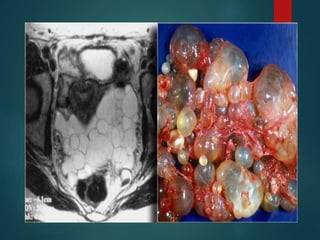

Peritoneal Inclusion Cyst…

• Multilocular peritoneal inclusion cyst/Benign cystic

mesothelioma.

• Occurs in premenopausal women with prior

gynocolical surgery or infection that results in

peritoneal scarring.

• The hormonally active ovaries secrete fluid that

becomes loculated in pelvis.

44Y/F

H/O Cystectomy

Pelvic mass

Peritoneal Inclusion Cyst… •Multilocular peritoneal inclusion cyst/Benign cystic mesothelioma. • Occurs in premenopausal women with prior gynocolical surgery or infection that results in peritoneal scarring. • The hormonally active ovaries secrete fluid that becomes loculated in pelvis.

• #24 Imaging feature is nonspecific..seen at Multicystic pelvic mass Enhancing septa Peritoneal surfaces of uterus,bladder may extend upp abd. Tvs demonstrating a multicystic pelvic lesion next to uterus which proved to be a peritoneal inclusion cyst. Sometime the ovary is seen trapped with the septate flid collection.

• #25 Nice corrlation betwwen mri and the specimen.